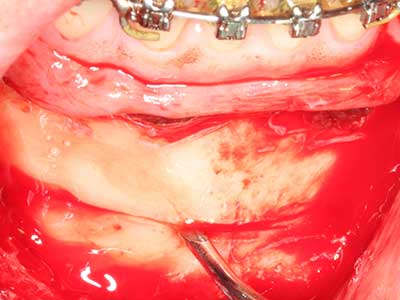

La piezochirurgia presenta altri vantaggi per quanto riguarda la raccolta di blocchi ossei. Oltre all'elevata precisione dell'osteotomia appena descritta, l'utilizzo di puntine per sega molto sottili permette di minimizzare in maniera significativa la perdita di materiale. È molto probabile che si verifichi una maggiore perdita di materiale durante la raccolta utilizzando puntine di strumenti più spessi, in particolare delle frese Lindemann (Lakshmiganthan, Gokulanathan et al. 2012). La separazione basale, necessaria in particolare per i trapianti di blocchi nella zona retromolare, viene semplificata grazie a seghe specificatamente progettate di forma rettangolare; di conseguenza la piezochirurgia è considerata una procedura precisa, semplice e sicura per la raccolta di blocchi di osso nella zona retromolare (Happe 2007) (figg. 1-12).